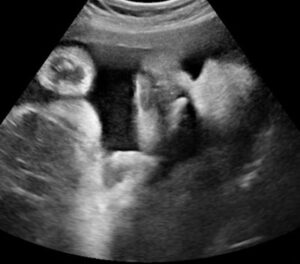

УЗИ на 32-34 неделе беременности: растем и готовимся к родам

Срок родов на 32 неделе беременности имеет решающее значение при определении тактики родоразрешения. Все важные показатели, степень зрелости легких, рост плода и его параметры, а также точный срок родов можно оценить с помощью УЗИ. Своевременно проведя это обследование, можно избежать опасных для плода естественных родов и снизить последствия фетоплацентарной недостаточности. Сроки проведения третьего планового УЗИ …